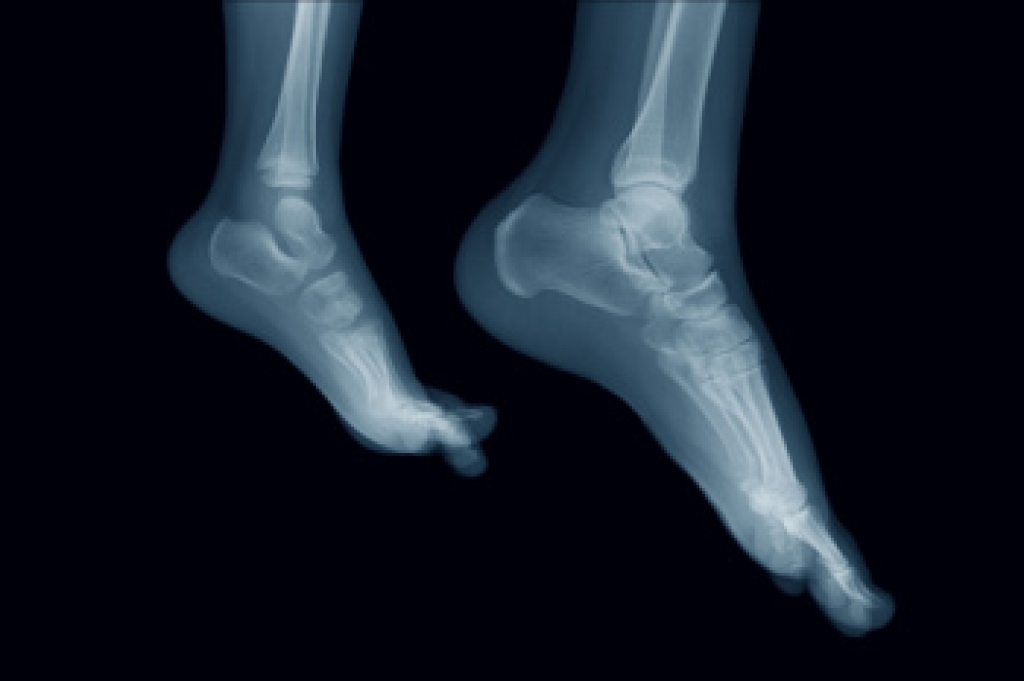

Falls are a significant concern for older adults, as they can lead to serious injuries and a decline in overall health. Several risk factors contribute to falls in this age group, including a fear of falling, which can limit mobility and lead to a decline in physical activity. Loss of strength and balance also increases the risk of falling, as muscles weaken with age. Poor vision, medications that cause dizziness, and environmental hazards such as slippery floors or poor lighting further elevate the risk. To prevent falls, older adults should engage in strength and balance exercises to maintain mobility and flexibility. Wearing proper footwear with a good grip can also help prevent slips. Removing hazards from the home, such as rugs or clutter, and installing grab bars in key areas can make the living environment safer. Regular eye exams and medication reviews are also important in reducing fall risks. If you have sustained a foot injury from falling, it is suggested that you consult a podiatrist who can offer you effective relief and treatment solutions, and guide you on successful fall prevention tips.